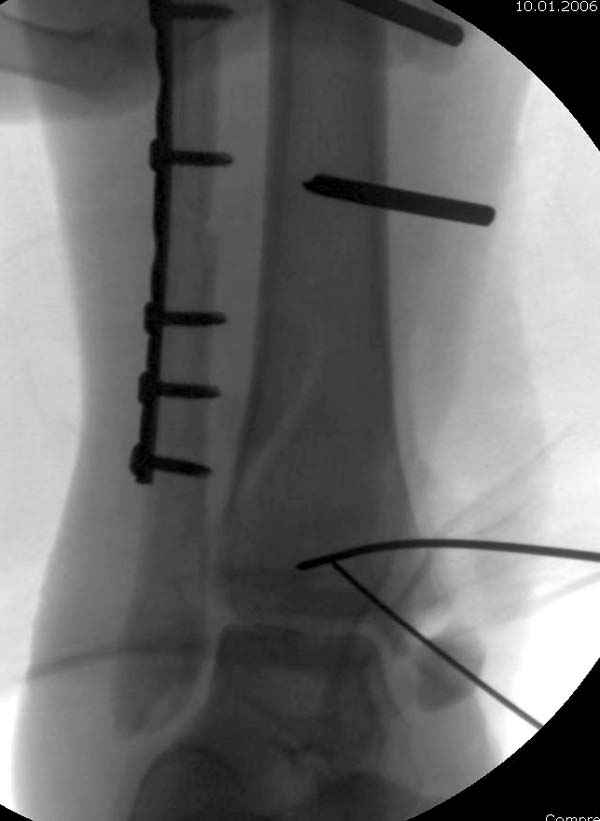

Из заднего доступа остеотомия тонким остеотомом и коррекции на ЭОПе.

Без применения сложной конструкции, а обычными параллельными шурупами. Шурупы в 3.5 мм и дополнительно фиксация крючковидной пластиной, сделанной из 3.5 mm semitubular пластиной, Butress или аntiglade фиксация.

Здесь алгоритм фиксации свежего перелома и преоперационный план для обсуждаемого случая.